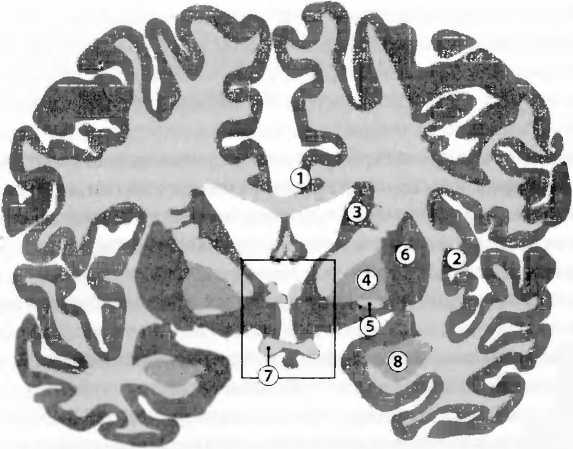

Рис. 26. 1) Цингулярная (поясная) кора, область треноги; 2) инсулярная (островковая) кора, активная при эмоциональных переживаниях, координирует телесные, автономные реакции; 3) nucleus caudatus (хвостатое ядро), моторика и эмоции; 4) globus palliclus (бледный шар), моторика; 5) ventral pallidum/nucleus accumbens (вентральные отделы бледного шара/прилежащее ядро), вознаграждение; 6) putamen (скорлупа), моторика; 7) оптическая хиазма, пересечение ’зрительных не рвов: 8) миндалевидное тело, страх, агрессия и сексуальное поведение. Гипоталамус заключен в рамку.

У японских монахов, как показала функциональная томография, различные виды медитаций стимулировали различные области мозга. Речь идет о частях префронтальной коры (рис. 14) и латеральной, теменной коре (рис. 1). Кроме того, религиозные убеждения сочетаются с меньшей активностью передней части циркулярной (поясной) коры (АСС, anterior cingulate cortex, рис. 26), что отмечается также и для политического консерватизма. Хотя причины этих соотношений неясны, интересно, что проявление инициативы сочетается с повышенной активностью в АСС. На электроэнцефалограмме (ЭЭГ) монахинь-кармелиток отмечались сильные изменения во время мистических переживаний. Мистическое переживание заключается в чувстве единения с Богом. При этом человек верит, что обрел последнюю истину, у него исчезает ощущение пространства и времени, он чувствует единство с человечеством и вселенной, его охватывает чувство мира, радости и бесконечной любви. Нейрофармакологические исследования указывают на то, какое большое значение для этих переживаний имеет активация дофаминовой системы вознаграждения (рис. 15). Болезни мозга также дают здесь существенную информацию. Так, болезнь Альцгеймера связана с возрастающей утратой религиозного интереса. Чем медленней развивается эта болезнь, тем меньше она затрагивает степень религиозности и спиритуальности. Гиперрелигиозность, напротив, обнаруживается при лобно-височной деменции, мании, обсессивно-компульсивных расстройствах (навязчивых состояниях), шизофрении и височной эпилепсии. О некоторых из этих болезней известно, что они сопровождаются повышенной активностью дофаминовой системы вознаграждения.

При проведении функциональной томографии монахинь-кармелиток просили вспоминать о своих мистических переживаниях. Когда монахини заново воссоздавали их в своем воображении, возникала сложная картина активности различных областей мозга: (i) активация средней части височной доли, что может быть связано с чувством единения с Богом, — эта область активируется также при височной эпилепсии, при которой могут возникать сильные религиозные переживания (рис. 27); (in активация хвостатого ядра (nucleus caudatus, рис. 26), области, где обрабатываются эмоции, что может быть связано с переживанием чувства радости и бесконечной любви; (iii) активация стволовой части мозга (рис. 20), инсулярной (островковой) области мозга (рис. 26) и префронтальной коры (рис. 14), что может быть связано с автономными телесными реакциями, сопровождающими эти эмоции и их осознание в коре. При этом происходила (iv) активация латеральной теменной коры, что может быть связано с чувством изменений в телесной схеме, близким околосмертному состоянию (рис. 27).